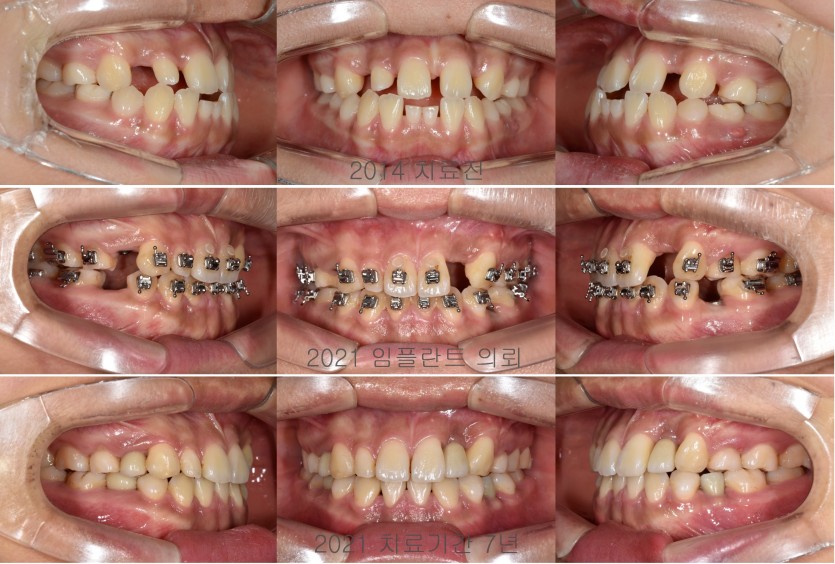

다수 결손치의 교정치료 170회

다수치아가 결손되었다고 내원한 초등학생은 치료기간이 매우 길어집니다.

결손된 치아들을 교정치료만으로 해결하기 어렵기 때문에 성장이 종료된 뒤 임플란트 수복등이 진행되어야하기 때문입니다.

그러나, 결손치의 공간을 효율적으로 해결하기 위하여 잔존하는 영구치들을 배열이 중요합니다.

더불어 임플란트 수복을 담당하는 치과의사와 의견교환과 협진이 잘 이뤄져야 합니다.